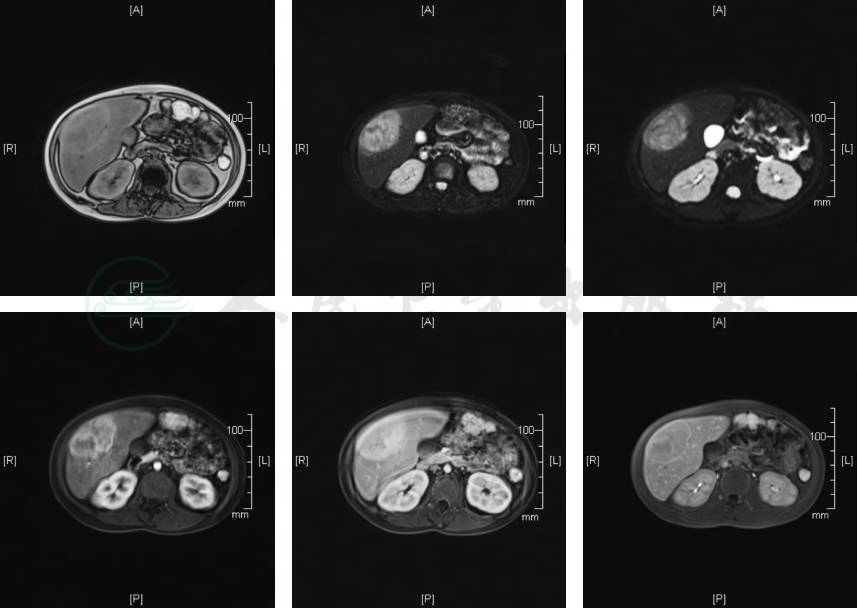

肝脏MRI检查(图1):①肝脏多发占位:考虑腺瘤可能性大,最大一枚(肝右前叶下段)恶变不除外,请结合临床进一步检查;②肝脏弥漫性多发增生结节可能性大,随访;③肝大,脂肪肝。

图1 肝脏MRI检查

第一排从左到右依次是T1W1、T2W1、DWI;第二排从左到右依次是增强动脉期、增强门脉期、增强肝胆特异期。